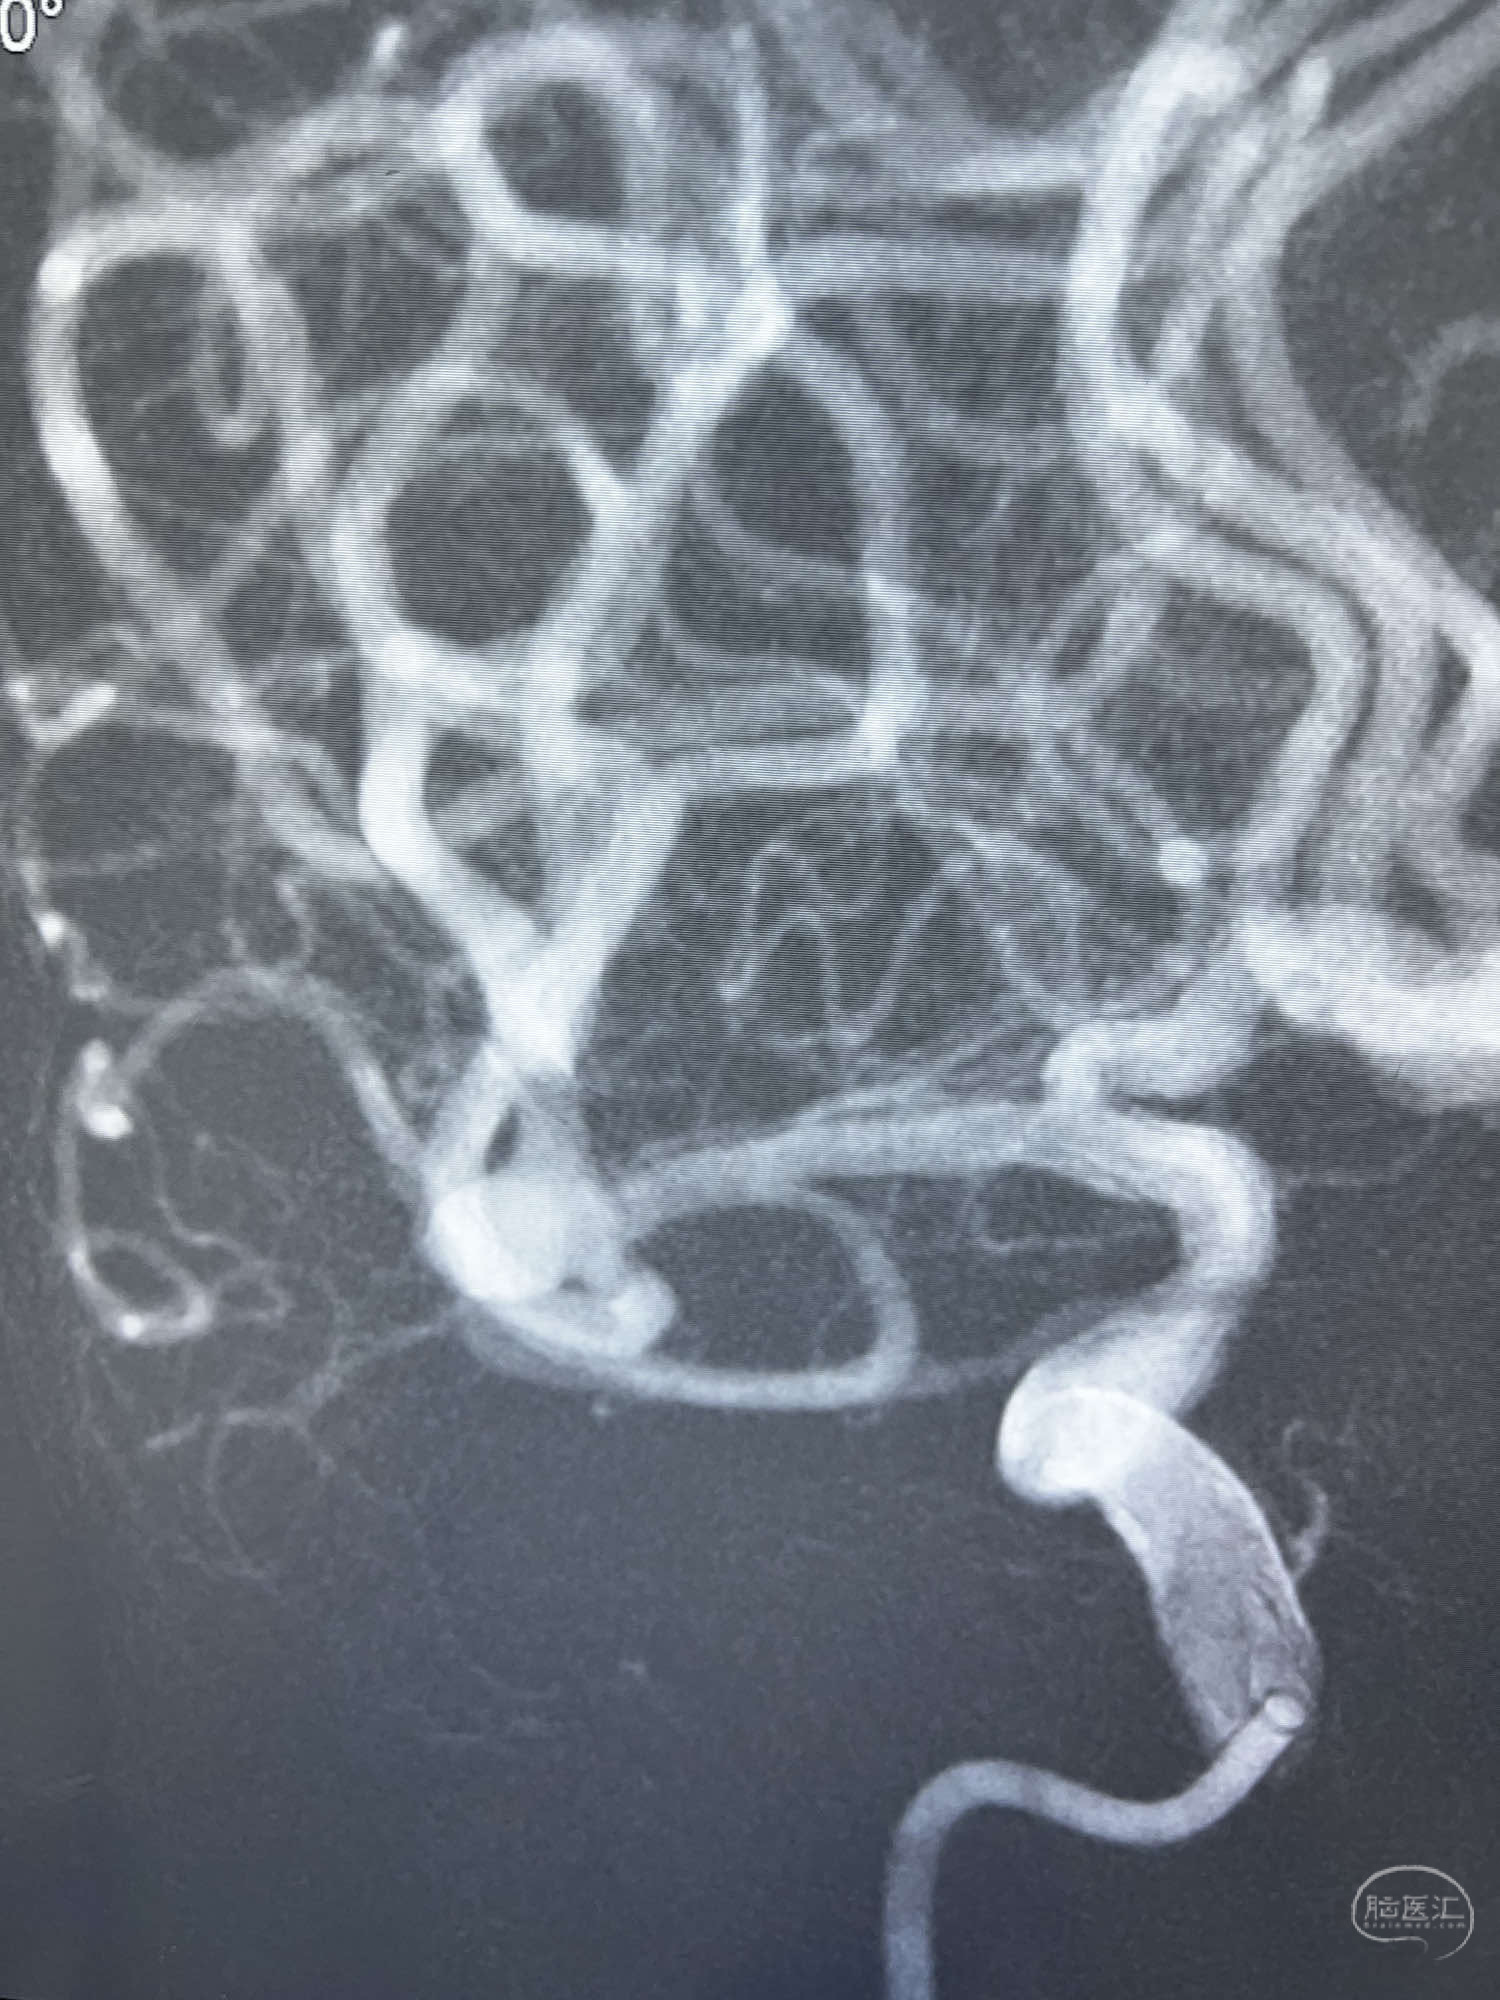

6F Neuromax➕6F115cm 心玮中间导管建立路径,sychro14微导丝➕VIA21超选至动脉瘤体内近中部,WEB5mmx3mm植入动脉瘤。

WEB瘤内扰流装置5mmx3mm经过“种子、萌芽、开花”三个阶段,打开后良好贴壁,动脉瘤内血液滞留,载瘤动脉通畅。WEB一步到位,通过瘤内扰流的方式起到栓塞动脉瘤的作用,避免了应用支架保护分支血管,简化了操作步骤,降低了术中血栓及出血的风险。